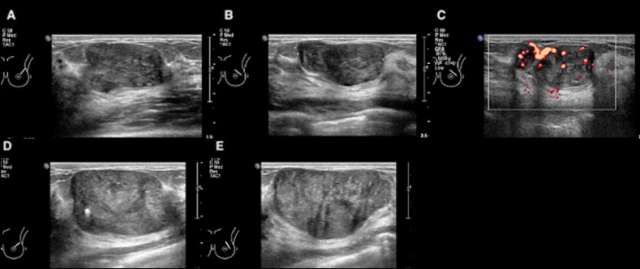

Figure 1. 31-year-old female presents with a palpable abnormality in the left breast 2:00 position 3 centimeters from the nipple. Targeted sonography in June 2020 (A-C) revealed a 3.0 x 1.7 x 3.0 cm circumscribed irregular mass with hypervascularity. A biopsy was performed with a pathologic diagnosis of “cellular fibroepithelial lesion”. Repeat sonography in September 2021 (D-E) showed interval increase in size of the left breast mass, measuring up to 4.5 x 2.6 x 3.8 cm. Surgical consultation was recommended with subsequent lumpectomy. Final pathologic diagnosis revealed phyllodes tumor.